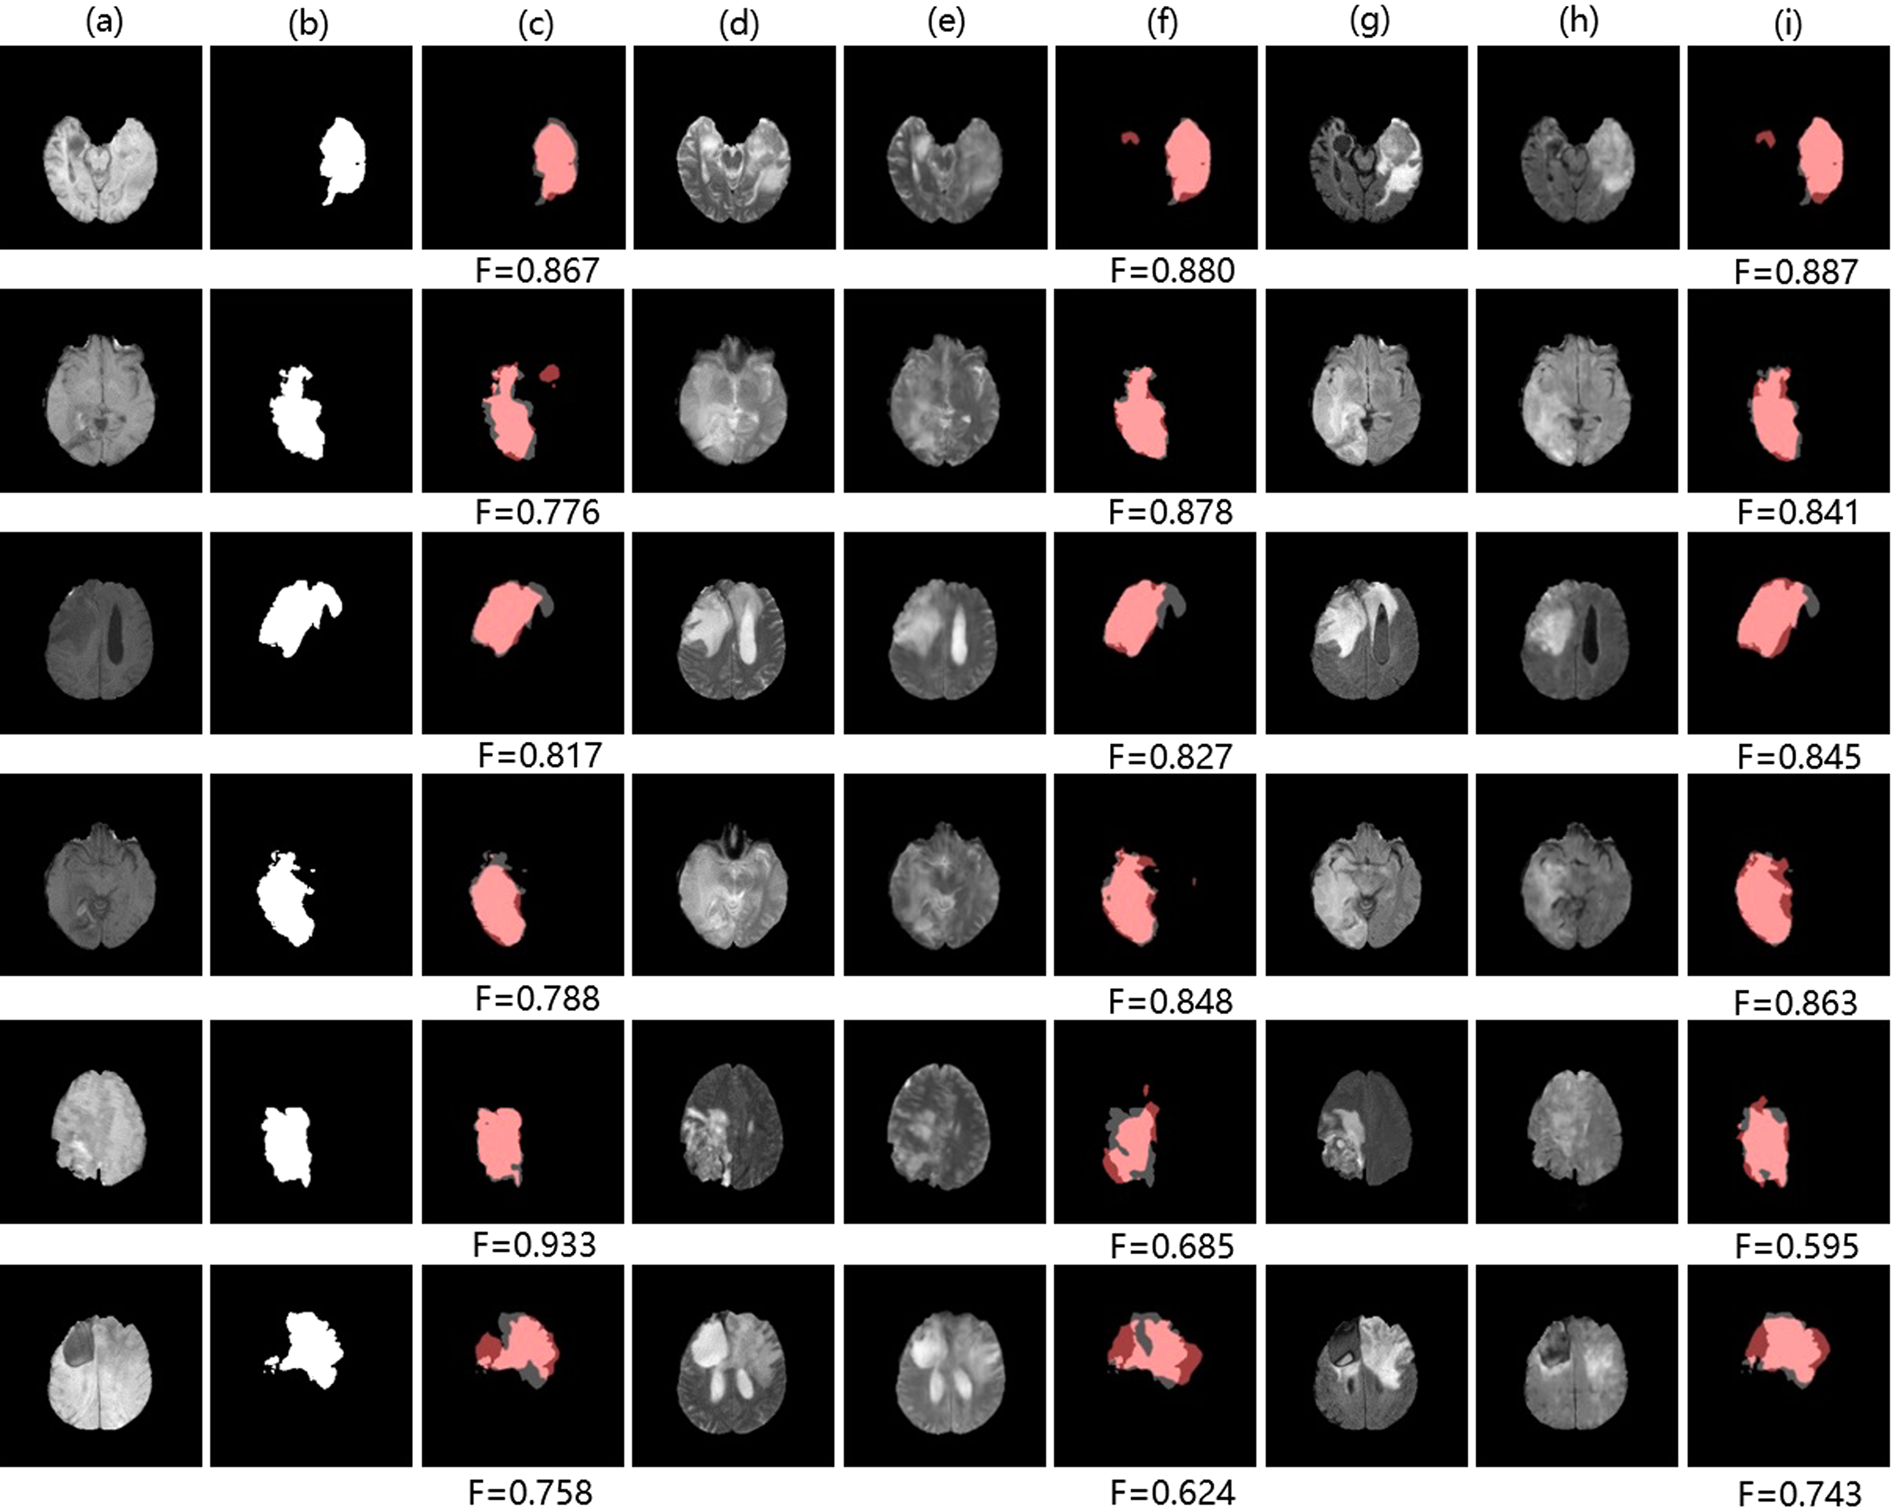

Figure 9

Samples of tumor segmentation results on BraTs2015: (a,d,e,g,h) denote T1 image, T2 image, \(\widehat{T}2\) image, T2-Flair image, \(\widehat{T}2\)-Flair image. (b) Denotes ground truth segmentation label of T1 image. (c,f,i) Denote tumor segmentation results of T1 image using the FCN method, TMS (adding cross-modality information from \(\widehat{T}2\) image), TMS (adding cross-modality information from \(\widehat{T}2\)-Flair image). Pink: true regions. Grey: missing regions. Dark red: false regions.